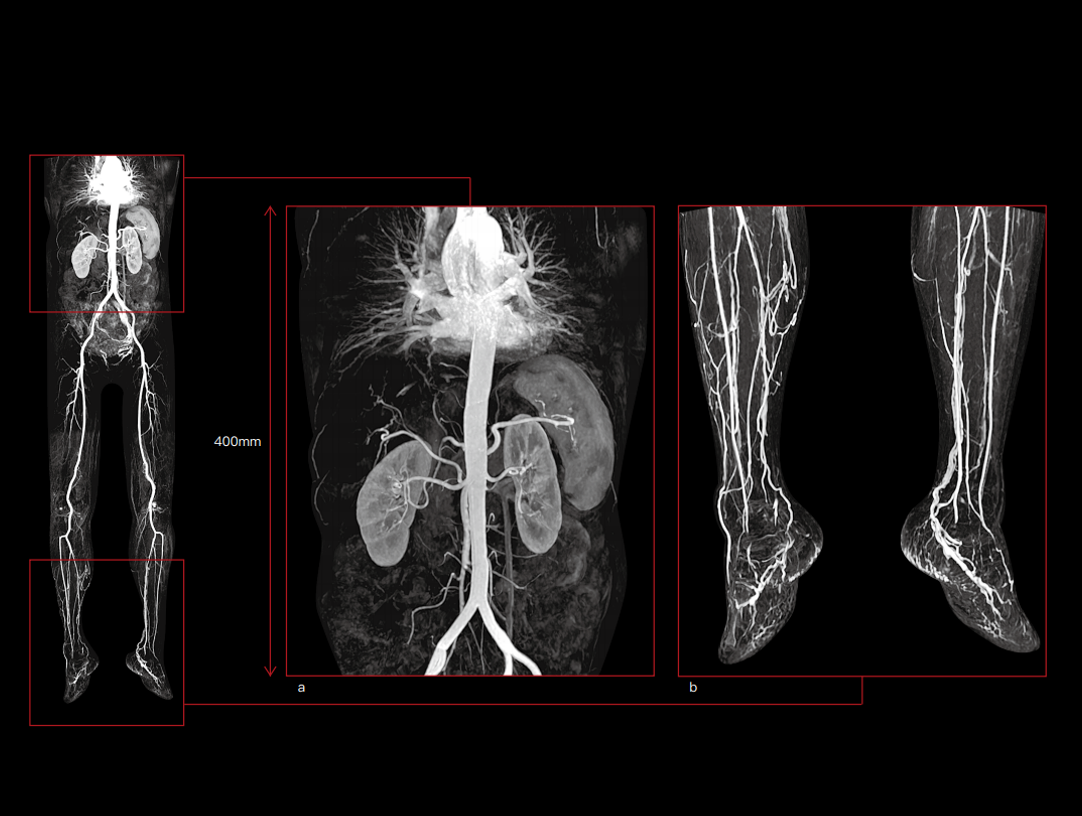

- Media